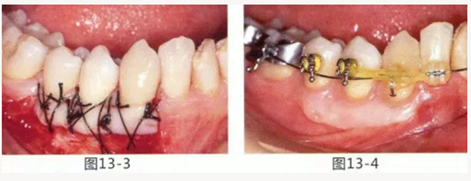

圖14-1 修復體周圍角化牙齦較少,很難進行清潔的狀態(tài),并有緣下齲壞的發(fā)生。

圖14-2,3 徹底去除齲壞后,試圖通過游離齦移植獲取生物學寬度和附著齦。

圖14-4~6修復體周圍角化牙齦較少,很難進行清潔的狀態(tài),并有緣下齲壞的發(fā)生。

圖14-7 配戴最終修復體完成5年后的狀態(tài)。保持良好。